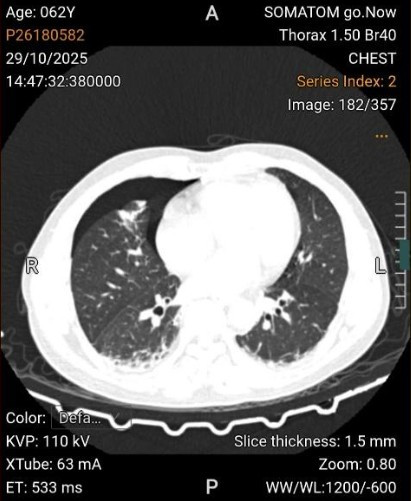

Hình ảnh dị vật trên phim chụp - Ảnh BVCC

Một ca cấp cứu nghẹt thở vừa được các bác sĩ Khoa Cấp cứu Tiêu hoá, Bệnh viện Trung ương Quân đội 108 (Bệnh viện TWQĐ 108) xử trí thành công: Dị vật nhựa cứng, sắc nhọn hai đầu, dài gần 4cm, xuyên thủng 2 thành thực quản đoạn ngực và gây tràn khí trung thất, tràn khí màng phổi phải.

Theo đó, bệnh nhân N.V.N (62 tuổi) nhập viện với đau ngực phải, đau thượng vị kéo dài 3 ngày. Bệnh nhân đã nội soi lấy dị vật nhưng thất bại.